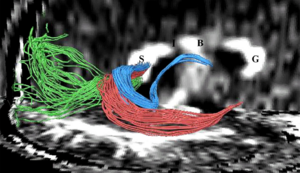

Seeing More by Showing Less: Orientation-Dependent Transparency Rendering for Fiber Tractography Visualization

Publication: PLoS One. 2015 Oct 7;10(10):e0139434. PMID: 26444010 | PDF Authors: Tax CM, Chamberland M, van Stralen M, Viergever MA, Whittingstall K, Fortin D, Descoteaux M, Leemans A. Institution: Image Sciences Institute, University Medical Center Utrecht, Utrecht, The Netherlands. Background/Purpose: Fiber tractography plays an important role in exploring the architectural organization of fiber trajectories, both in fundamental neuroscience and in clinical applications. With the advent of diffusion MRI (dMRI) approaches that can also model "crossing fibers", the complexity of the fiber network as reconstructed with tractography has increased tremendously. Many pathways interdigitate and overlap, which hampers an unequivocal 3D visualization of the network and impedes an efficient study of its organization. We propose a novel fiber tractography visualization approach that interactively and selectively adapts the transparency rendering of fiber trajectories as a function of their orientation to enhance the visibility of the spatial context. More specifically, pathways that are oriented (locally or globally) along a user-specified opacity axis can be made more transparent or opaque. This substantially improves the 3D visualization of the fiber network and the exploration of tissue configurations that would otherwise be largely covered by other pathways. We present examples of fiber bundle extraction and neurosurgical planning cases where the added benefit of our new visualization scheme is demonstrated over conventional fiber visualization approaches. Funding: